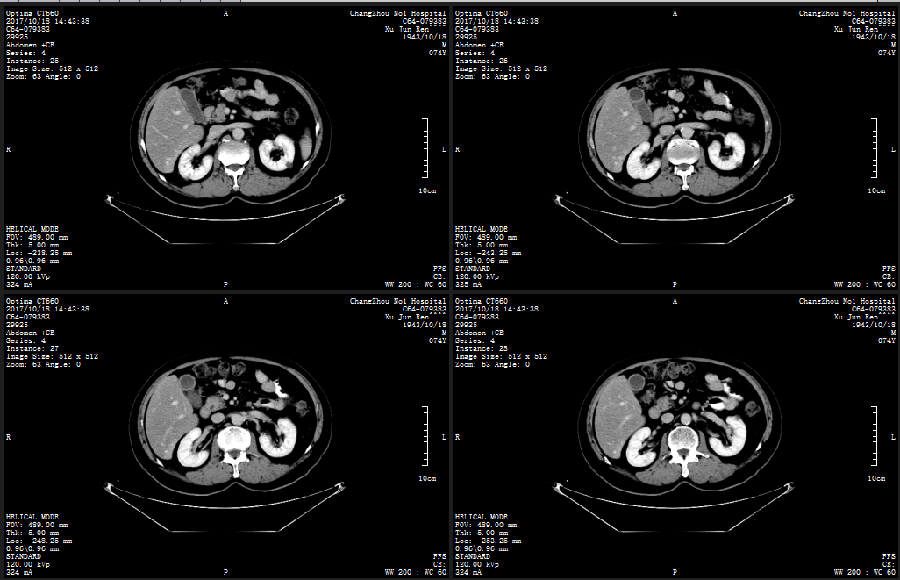

CT:2017-10-18

SD